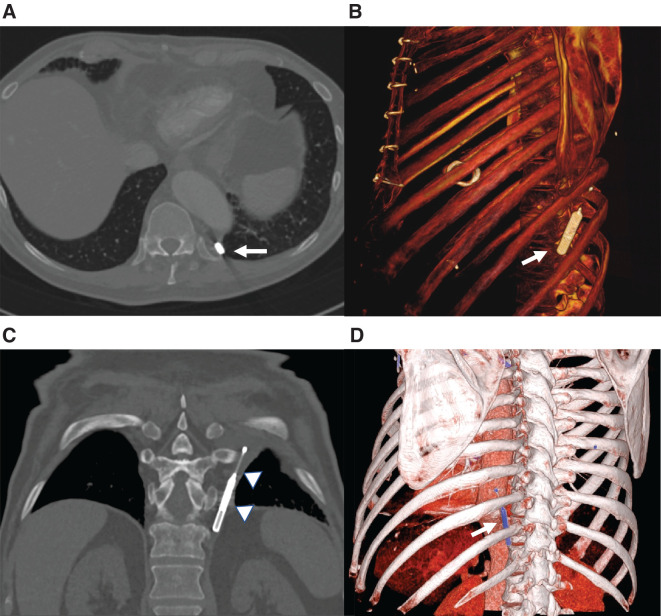

The migration of an implantable loop recorder (ILR) is a rare complication. We aimed to perform a meta-summary of case reports to characterize patients who experienced an ILR migration. We searched for case reports published in PubMed, Google Scholar, Scopus, and Embase from January 2017 to 2023 using the following keywords: "migration ILR," "migration loop recorder," "complication loop recorder," and "complication ILR." Seven case reports/case series reporting ILR migration were included. Data about patients' characteristics, ILR implantation, time of onset, management, and clinical outcome of this complication were collected. Seven patients who experienced the migration of an ILR were examined. All patients experienced migration within 35 days following ILR implantation. The clinical suspicion of ILR migration mainly arose from patients' symptomatology. The migration of the ILR was confirmed by a radiological scan in all cases, and surgical removal, preferably by video-assisted thoracic surgery, was required. In conclusion, intrapleural migration is a rare complication of ILR implantation. It may occur in the early postprocedural period. Clinical suspicion arises from symptoms, but a radiological scan is necessary to confirm the diagnosis. Surgical removal is mandatory.